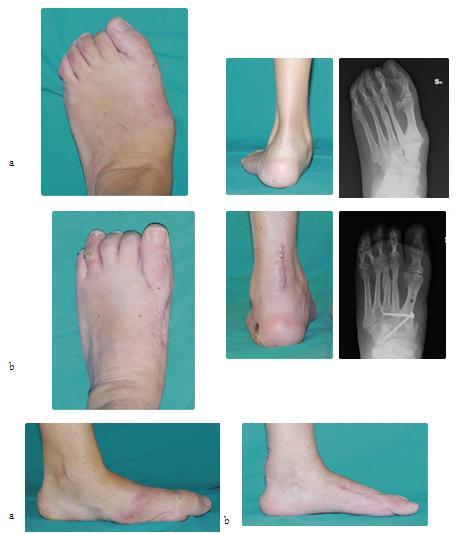

Caso 3: Piede cavo in malattia di Charcot-Marie-Tooth

Maschio, 15 anni, piede cavo secondario da malattia di Charcot-Marie-Tooth (a). Sottoposto a correzione chirurgica del piede sinistro mediante intervento di fasciotomia plantare, osteotomia del tarso, trasposizione del tendine estensore lungo dell'alluce secondo tecnica di Jones ed osteotomia di sollevamento del primo metatarso (b). La tecnica chirurgica è stata presentata come Scientific Exhibit all'AAOS 2014. Riconosciuto come uno dei migliori lavori del convegno è stato selezionato per la pubblicazione sulla rivista Journal of Bone and Joint Surgery American. Il video di questo intervento verrà presentato come multimedia educational all'AAOS 2015.

Caso 7: Piede piatto associato ad alluce valgo giovanile

Femmina di 11 anni affetta da piede piatto bilaterale e alluce valgo (a). Sottoposta ad intervento chirurgico di artrolisi dell'articolazione sottoastragalica con impianto di endortesi endosenotarsica riassorbibile secondo Giannini e asportazione di scafoide accessorio con tensionamento del tibiale posteriore, associato a osteotomia correttiva del primo metatarso con tecnica S.E.R.I. (b). Ottimo risultato clinico, funzionale e radiografico.